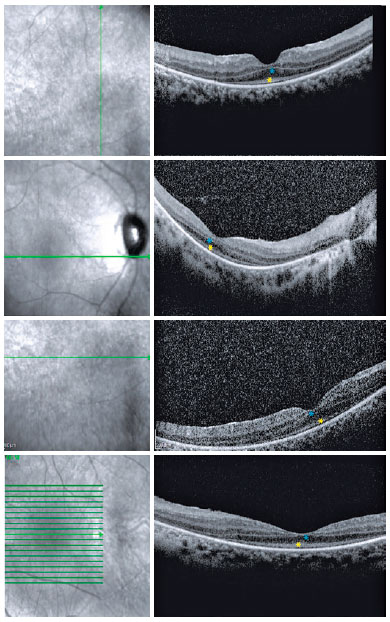

Fundoscopic findings showed optic disc pallor, narrowing of retinal vessels, and peripheral bone spicules (only in cases 3 and 4) in OU of all patients. FAF showed smooth hyper/hypoautofluorescence macular mottling (Figure 1), while SD-OCT demonstrated, in all cases, areas of outer retinal layer atrophy and central retinal thinning (Figure 2). Electrooculography demonstrated an Arden index of >1.8, besides absence of ERG registered scotopic and photopic stimuli (ARSP) responses with reduction of flicker electroretinography at 30 Hz. Reduction of amplitude and preserved latency occurred in evoked visual potential (Table 1, Figures 3 and 4).

There was positive correlation between morphological and functional findings. That is, retinal dystrophy and associated retinal findings, as assessed by SD-OCT, were in agreement with the electrophysiological findings. SD-OCT analyses demonstrated a single layer of undifferentiated and immature photoreceptors in the foveal zone with atrophy mainly of the peripheral retinal external layers (Figure 2). In addition, abnormal persistence of internal retinal layers occurred in the central foveal zone. Changes in FAF are poorly standardized in AS. In the presented cases, however, there was evidence of hyperautofluorescence areas and hypoautofluorescence spots suggesting, respectively, involvement and atrophy of retinal pigment epithelial cells. Electrophysiology demonstrated early dysfunction followed by rapid rod deterioration in advanced stages of disease with no response to scotopic and photopic stimuli leading a mixed dysfunction of photoreceptors(10) (Figures 1 and 3).